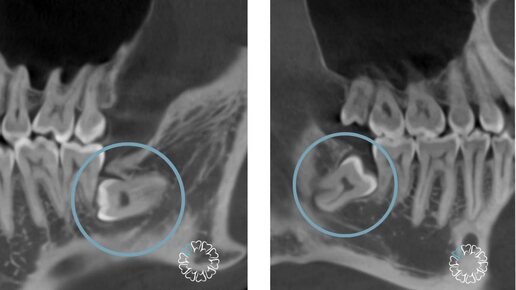

Удаление зубов мудрости — не самая сложная операция в стоматологической практике, но для многих людей она кажется страшной и вызывает массу вопросов. Стоматолог «Белой радуги» Журов Илья Владимирович рассказывает, как должна проходить процедура удаления зубов мудрости, чтобы у пациента не было осложнений, а ее последствия не привели к проблемам с зубами в будущем. В статье он ответит на вопросы: Этап 1. Сбор анамнеза и осмотр перед удалением зубов мудрости Когда у человека болит зуб мудрости, он...